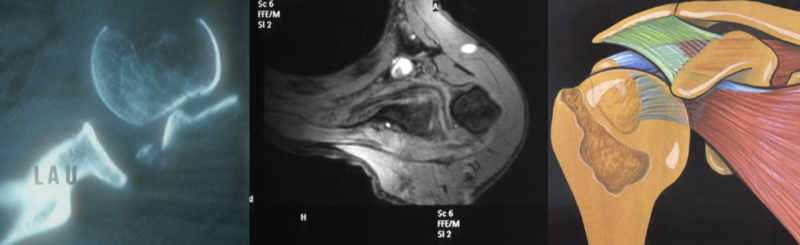

RC incarceration